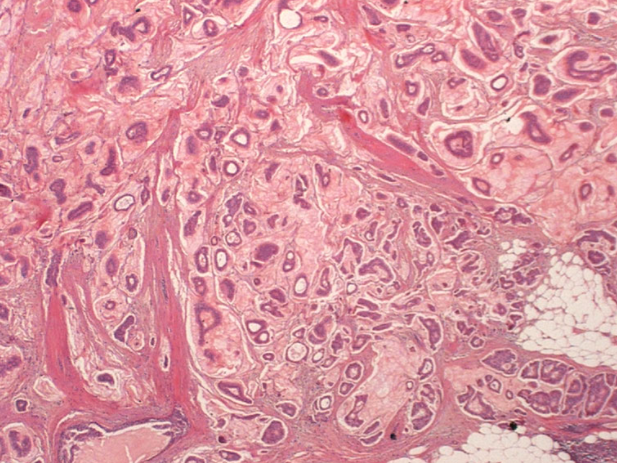

What type of breast cancer is shown?

Invasive ductal carcinoma